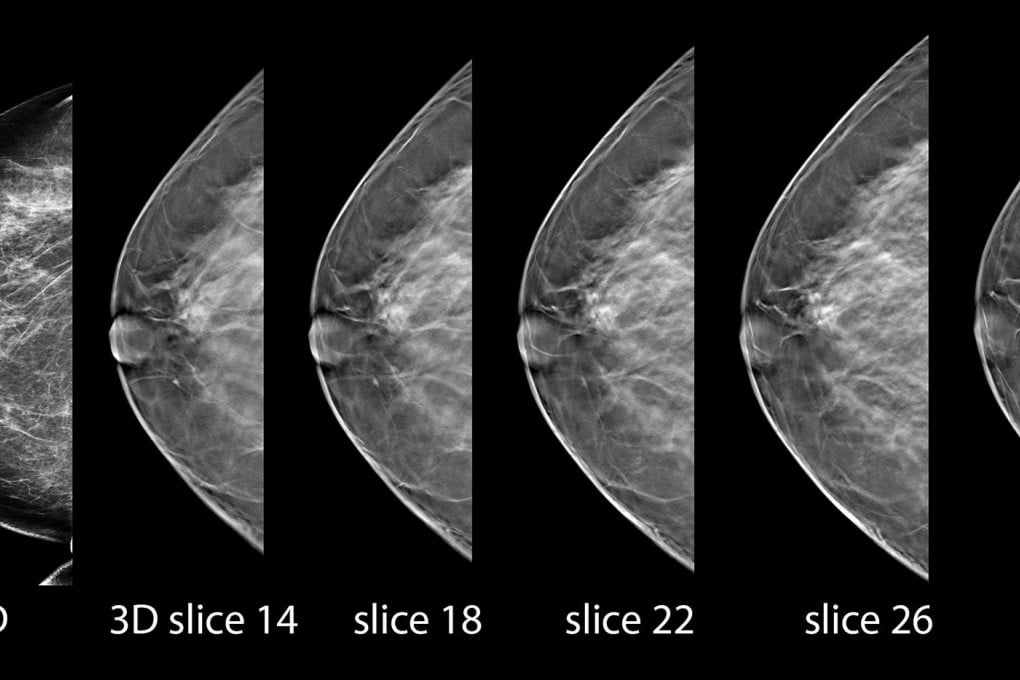

In addition, there's not enough evidence to tell if new 3-D mammograms are the best option for routine screening, or if women with dense breasts need extra testing to find hidden tumours, the US Preventive Services Task Force has concluded.